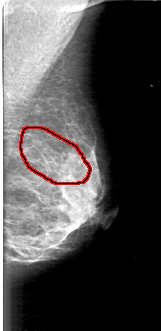

FILE: D_4168_1.LEFT_MLO.OVERLAY

TOTAL_ABNORMALITIES 1

ABNORMALITY 1

LESION_TYPE CALCIFICATION TYPE AMORPHOUS DISTRIBUTION SEGMENTAL

ASSESSMENT 0

SUBTLETY 4

PATHOLOGY BENIGN

TOTAL_OUTLINES 1

BOUNDARY